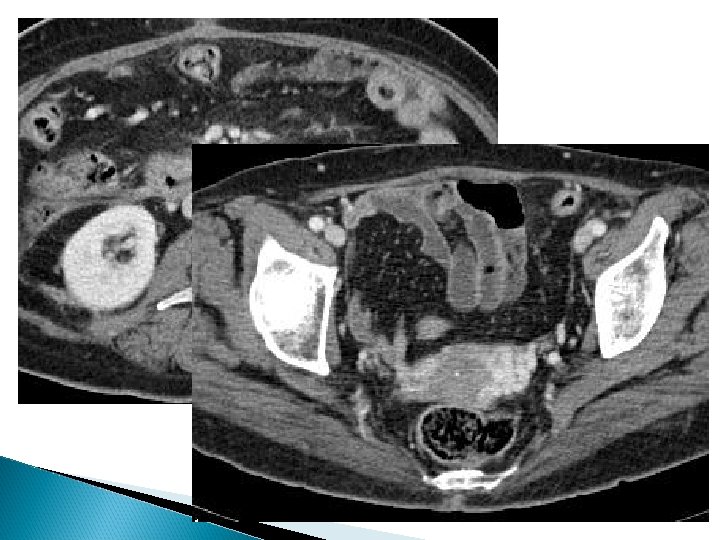

Tanı USG ◦ Transvaginal veya transabdominal Kesitsel görüntüleme ◦ BT ve MRG Selektif ovaryan ve internal iliyak venografi

perkütan embolizasyonskleroterapi Jugular veya femoral Sol renal venografi Selektif ovaryan venografi Pelvik kesime sklerozan tedavi Distal orta ve proksimal kesimlere koil embolizasyonu ◦ Kollateraller ve varyasyonlar ! Sağ ovaryan venografi ◦ Reflü varsa aynı şekilde embolizasyon